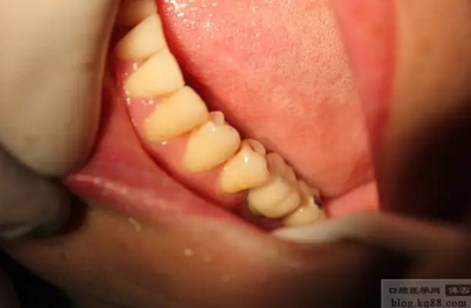

右上后牙外提升

直接上基臺做臨時樹脂橋體,即刻負重